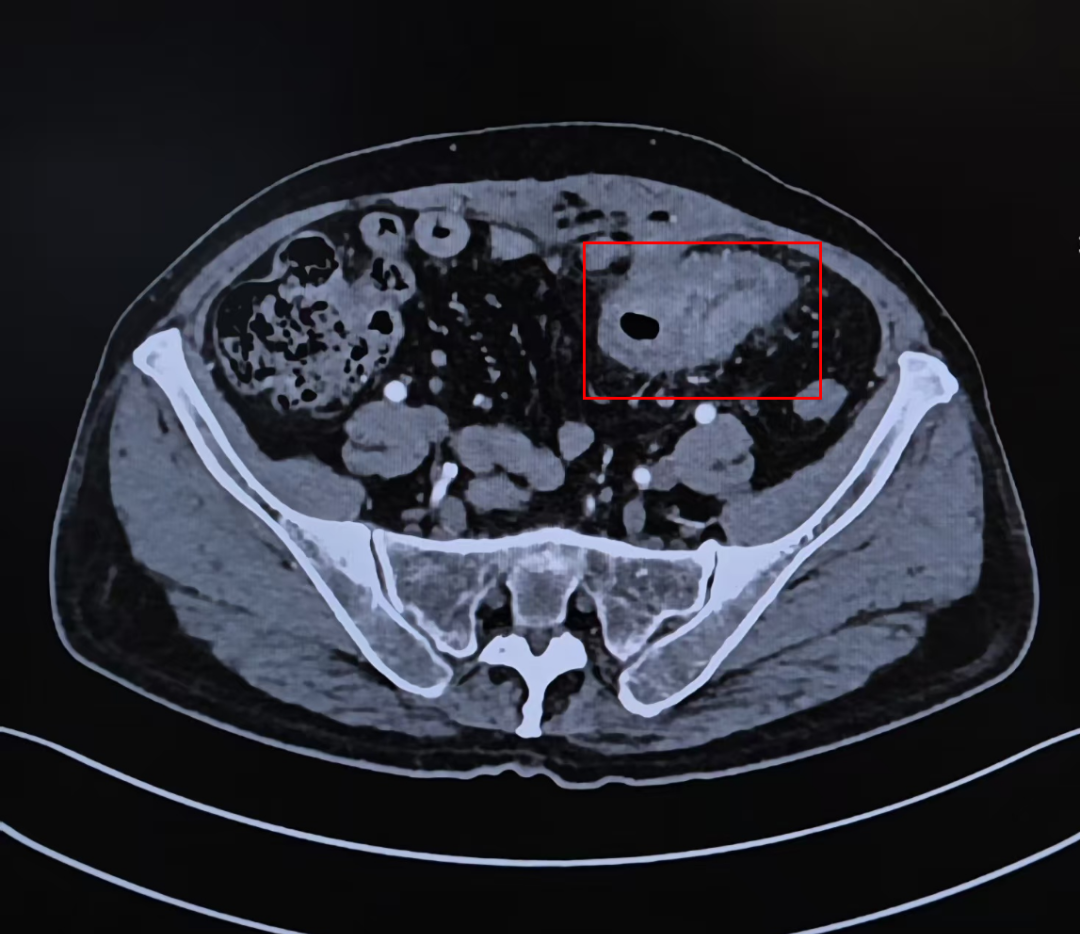

2月21日,宋禾副教授团队顺利为患者完成横结肠双腔造口术,肠梗阻症和结肠膀胱瘘的症状即刻缓解,为后续治疗赢得时间。肿瘤内科徐玲教授团队根据基因检测结果,结合患者肝肾功能、心肺状态,联合麻醉科评估耐受度,最终确定西妥昔单抗联合mFOLFOX的方案。治疗期间,徐玲教授团队密切监测,通过对比肿瘤大小变化调整药物剂量;临床营养科根据患者食欲减退情况定制高蛋白食谱,配合护理团队监测体重变化。3个周期后,患者影像学复查结果提示肿瘤体积明显缩小,膀胱侵犯范围由之前的广泛侵犯到现在的局限侵犯,MDT团队一致判定达到根治手术条件。

CT显示经过新辅助治疗之后,乙状结肠恶性肿瘤体积以及侵犯范围明显缩小